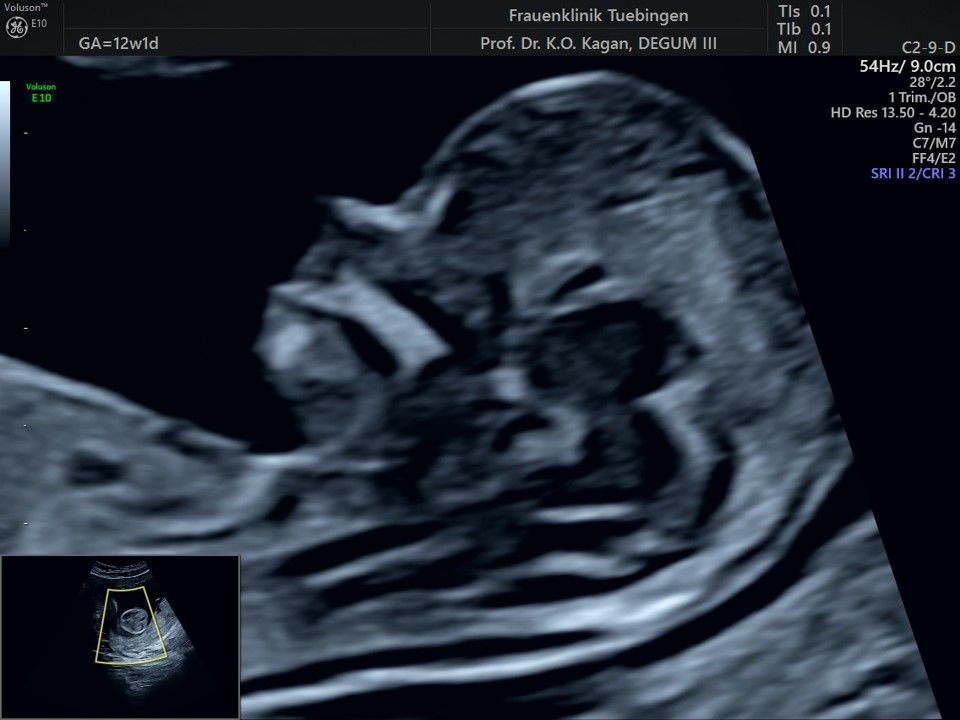

Im Rahmen des Ersttrimester-Screenings untersuchen wir die Organe des Feten mittels Ultraschall. Dabei machen wir auch gerne ein Bild für Sie.

Obwohl der Fet zu diesem Zeitpunkt erst zwischen 5 und 8cm groß ist, lassen sich bereits etwa die Hälfte aller schwerwiegenden Fehlbildungen erkennen bzw. ausschließen. Sollten wir eine Auffälligkeit sehen, werden wir mit Ihnen den Befund und das weitere Vorgehen ausführlich besprechen.